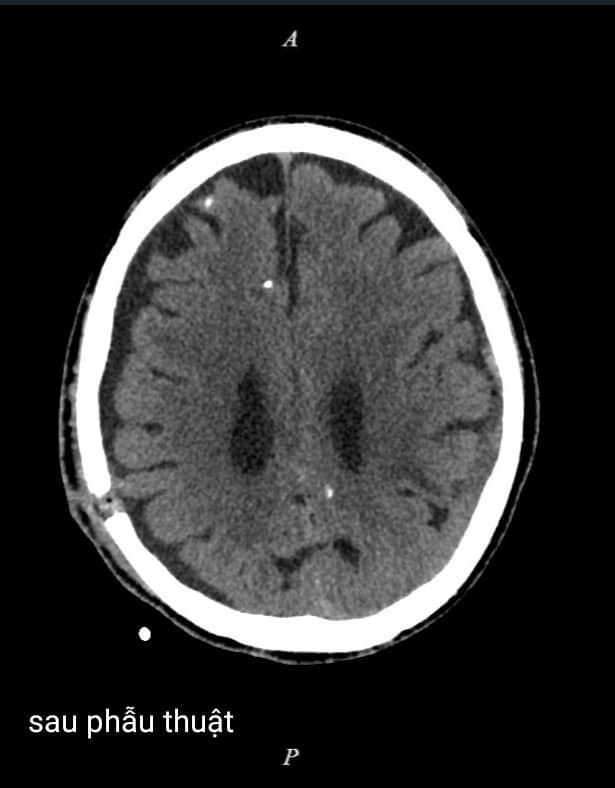

Bệnh nhân được mở sọ 01 lỗ, bơm rửa, dẫn lưu máu tụ. Sau phẫu thuật tình trạng sức khỏe của bệnh nhân ổn định và được ra viện.

| Hình ảnh chụp cắt lớp vi tính của bệnh nhân trước và sau phẫu thuật |

Ngày nay chẩn đoán xác định máu tụ dưới màng cứng mạn tính bằng máy chụp Cắt lớp vi tính và máy chụp Cộng hưởng từ cho kết quả chính xác cao, hiện đã có ở nhiều địa phương, rất thuận tiện cho chẩn đoán.